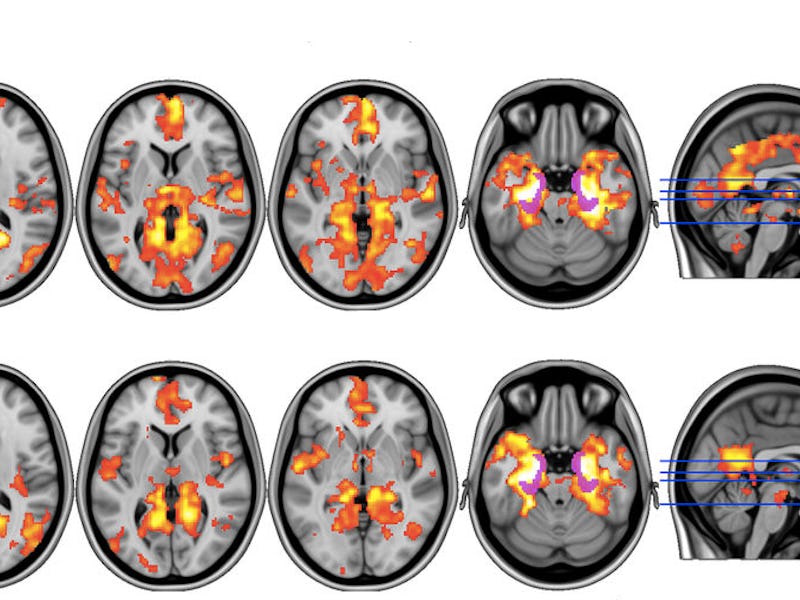

Before and after images of the brain after a dose of psilocybin show significant changes in blood flow.

This feeling of “resetting” seems to be linked to psilocybin’s ability to reduce blood flow to certain parts of the brain immediately following treatment. In the study, the 20 participants involved each received a 10-milligram dose of psilocybin one week, followed by a 25-milligram dose the next. On the days before and after they received the higher dose, their brains were scanned using a functional magnetic resonance imaging (fMRI) device, which visualizes the flow of blood in different regions in the brain.

An analysis of those scans showed that psilocybin changed blood flow in the amygdala, the part of the brain that’s thought to deal with emotions, like stress and fear.